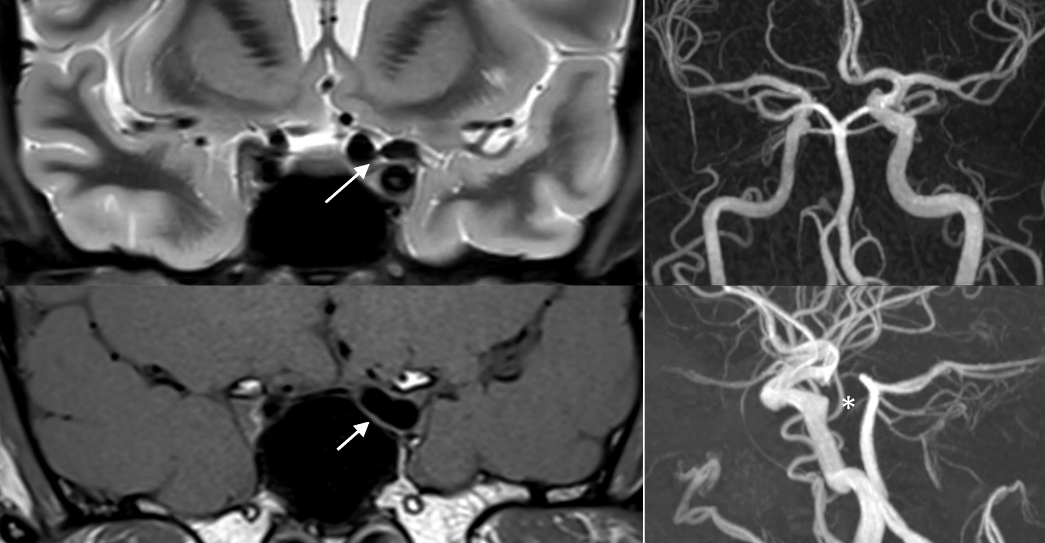

The MRI and MRI-angio (MRA) revealed a compression of the left optic nerve and chiasm by a dolichoectatic left supraclinoid internal carotid artery (Figure 2 [Fig. 2]).

Figure 2: On the left side both arrows show compression of the chiasm and left optic nerve by the dolichoectatic artery in the T2-weighted (above) and T1-weighted (below) MRI in coronal plane. On the right side the angiogram of the asymmetric internal carotid (above) giving rise to an ectatic and elongated left supraclinoid internal carotid artery and the absence of the right A1 segment (below, marked by *).

On the left side of the chiasm and distal optic nerve a dilated A1 segment of the left anterior cerebral artery and dilated anterior communicating artery with an absence of the right A1 segment were shown.

This likely congential asymmetric internal carotid artery gives rise to an ectatic and elongated left supraclinoid internal carotid artery, which compresses the chiasm and left optic nerve on the other side.